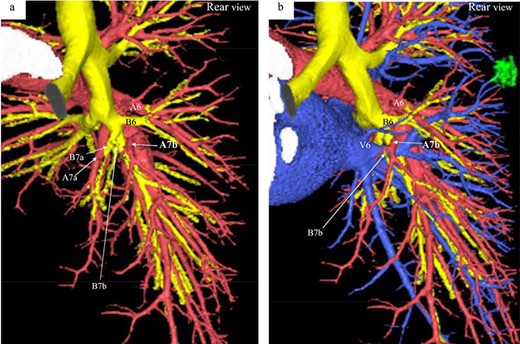

Three-dimensional CT angiography and bronchography images. (a) Rear-view CT angiography image of the PA and bronchi. (b) Rear-view CT image of the PA, PV, and bronchi. Reconstructed images of the pulmonary arteries (red), pulmonary veins (blue), bronchi (yellow) and tumor (green). A, pulmonary artery; B, bronchus; V, pulmonaryvein.

A 56-year-old man was referred to our department for a right lower ground-glass nodule (GGN). Computed tomography (CT) revealed a pure GGN measuring 12 mm in diameter in the S6 of the right lung (Fig. 1). A pathological diagnosis could not be determined via transbronchial tumor biopsy. Three months after the initial investigation, CT revealed that the GGN had not shrunk, and a highly differentiated adenocarcinoma was strongly suspected. No hilar or mediastinal lymph nodes, or other organ metastases were observed on positron emission tomography/CT, or contrast-enhanced magnetic resonance imaging of the brain. Preoperative 3D CT revealed an aberrant A7b branching from the basal pulmonary artery (PA) and running behind the V6 (Fig. 2). The A7a and A7b subsegmental pulmonary arteries were located on the ventral and dorsal sides of the basal vein, respectively. Because lung cancer was highly suspected, surgery was scheduled.

Only three case reports have detailed an abnormal A7 branching in patients who underwent lung resection [1–3]. One report showed an aberrant mediastinal inferior lobar branch [A6 + the common basal artery (A7–10)] originating from the right main PA [1]. The remaining two reports also revealed A7 branching from the right main PA in patients who underwent lung resection for lung cancer [2, 3]. In these cases, the A7 and A7a branched from the main PA and the A7b branched as usual from the A8 + 9 + 10. The present case is unique because only the A7b branched from the A8 + 9 + 10 and was located behind theV6.

According to a previous report, the branching pattern of the B7 and A7 can be classified into four types: B7a, B7ab, B7b, and BX7. The B7a type is more common (74.8%) than the B7ab (14.8%), B7b (4.8%) and BX7 types (5.6%) [4]. Of the least common A7b pattern type (4.8%), only seven cases (2.6%) had their A7b diverged from the cranial side of the V6, as in our case. In the present case, the PA pattern and bronchus branching were compatible with the B7ab type, in which there are two bronchi (B7a and B7b) and two arteries (A7a and A7b). To the best of our knowledge, no previous reports have detailed a B7ab type, where the A7b branches behind theV6.